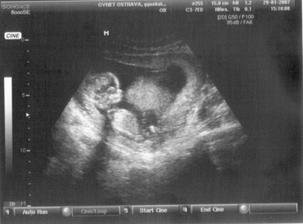

SRPŇÁTKA 2007 - fotky UTZ

album věnované mimískům, které se narodí v srpnu 2007 a jejich maminkám ze "Společného termínu SRPEN"